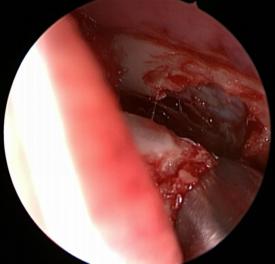

打開骨壁,暴露淚囊

切開淚囊

縫合鼻腔與淚囊黏膜